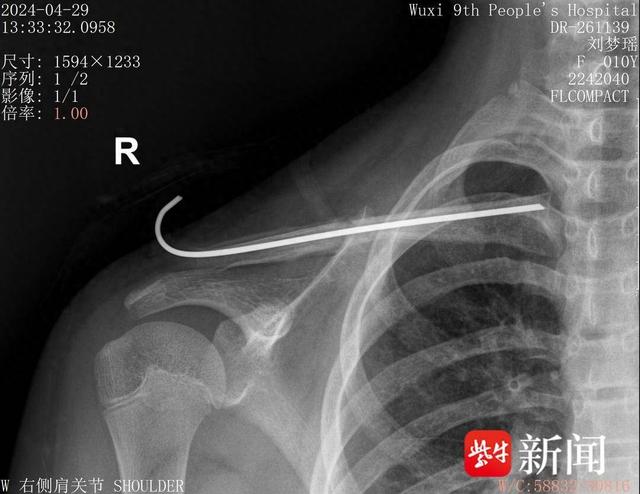

术后一个月骨愈合摄片患儿小紫(化名)因不慎摔伤,导致右侧锁骨干骨折

图片尺寸640x494

儿童锁骨骨折的治疗